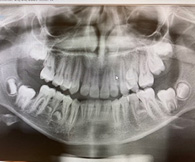

Autoras: Eugenia María Díaz Almenara. Doctora en Odontología. Sas. UGC Condado-Campiña. Esther Pérez Jiménez. Servicio Andaluz de Salud Email contacto: eugedial@gmail.com Resumen Los dientes supernumerarios representan una anomalía dental común, definida como la presencia de dientes adicionales superior al número normal previsto en la dentición temporal o permanente. La prevalencia se determina entre el 0,2 y el 3%, siendo más frecuente en los hombres que en las mujeres. Introducción La hiperodoncia o existencia de dientes supernumerarios se trata de una anomalía de número del desarrollo dental, en el que se pueden encontrar uno o más dientes adicionales de los 20 ó 32 normal de la dentición temporal o permanente respectivamente (1). La aparición de dientes supernumerarios es más frecuente en dentición permanente y en el maxilar superior, pudiendo presentarse de manera aislada o múltiple, unilateral o bilateral y afectar tanto al hueso maxilar como a la mandíbula (2). La etiología de esta alteración no está determinada con total exactitud, siendo la teoría más aceptada una hiperactividad de la lámina dental, junto a la asociación de factores genéticos, epigenéticos y ambientales (3). También se han asociado a la presencia de dientes supernumerarios algunos síndromes genéticos como el Síndrome de Gardner, fisura labiopalatina, poliposis adenomatosa familiar, Síndrome trichorhinophalangeal tipo I, Síndrome de Rubinstein-Taybi, Síndrome de Nance-Horan, Síndrome de Opitz G/BBB, Síndrome oculofaciocardiodental y Síndrome de Robinow (dominación autosómica) y la displasia cleidocraneal (4,5). La prevalencia de dientes supernumerarios en población no sindrómica es variable y depende del área geográfica, etnia y técnica de muestreo de la población estudiada (6, 7), coincidiendo múltiples estudios en que el sitio más frecuente en donde se presentan los supernumerarios es en el maxilar, con una predilección 2:1 por el sexo masculino (6,7,8). El diente supernumerario más común es el mesiodens, que se encuentra en la línea media del maxilar superior (9). Podemos clasificar los dientes supernumerarios según su posición en mesiodens, paramolares, parapremolares y cuartos molares; de acuerdo a la forma, en suplementarios o eumórficos y rudimentarios o dismórficos, pudiendo estos últimos ser de tipo cónico, tuberculado, molariforme y odontoma (10). Objetivo El objetivo del presente trabajo es realizar una revisión actualizada de la literatura sobre el manejo de los dientes supernumerarios, y reportar un caso clínico de un paciente que acudió a consulta de centro de salud pública situado en Huelva. Material y método Se realiza una revisión bibliográfica actualizada sobre dientes supernumerarios, utilizando bases de datos como Pubmed y Google Scholar. Palabras clave: hiperodoncia, dientes supernumerarios, mesiodens. Caso clínico Paciente varón de 11 años no sindrómico, sin antecedentes médicos relevantes, acude a una consulta dental pública de Huelva. El padre del paciente explica que en la Ortopantomografía previo al tratamiento de Ortodoncia, se han encontrado como hallazgo casual dientes supernumerarios en la mandíbula. En la exploración intraoral no se palpan inclusiones. En la Ortopantomografía se aprecian tres gérmenes de supernumerarios incluidos en la posición entre 35 y 36, entre 44-45, y entre 45-46 (Foto 1).  Se deriva al servicio de Cirugía Maxilofacial, donde solicitan un tac sin contraste de mandíbula, y valorar así la posición en 3d de los gérmenes respecto al canal del nervio dentario y las raíces de las piezas definitivas adyacentes. El informe del Tac identifica en el cuadrante inferior derecho (cuarto cuadrante) siete piezas dentarias erupcionadas. El diente 47 está parcialmente incluido en el proceso alveolar. El diente 48 se encuentra no erupcionado en estadio germinal. Se identifican 2 piezas dentales supernumerarias de aspecto germinal localizadas entre raíces de las piezas dentarias 44-45 y 45-46. Ambos gérmenes dentales se localizan superomedialmente respecto al canal dentario inferior derecho, sin relación directa con su luz, y medialmente a las raíces de las piezas dentales erupcionadas vecinas. La pieza dental germinal más posterior muestra incipientes formaciones radiculares que se ubican superiormente al canal dentario inferior homolateral. En el cuadrante inferior izquierdo (tercer cuadrante), se identifican igualmente 7 piezas dentales erupcionadas, con el diente 37 parcialmente incluido en el proceso alveolar. La pieza dental 38 no está erupcionada. Se identifican dos piezas germinales de dientes supernumerarios localizadas entre las raíces de las piezas dentales 33-34 y 35-36, localizadas medialmente a las raíces de las piezas dentales erucionadas vecinas. La pieza germinal más anterior no preserva contacto con el canal del nervio dentario que se origina posteriormente. La pieza germinal más posterior presenta incipientes raíces dentales que parecen contactar en su margen inferior con la pared superior del canal dentario inferior izquierdo. (Fotos 2,3).   El equipo de cirugía maxilofacial de Huelva decide la exodoncia de dientes supernumerarios para evitar complicaciones futuras. Discusión La localización adecuada de los dientes supernumerarios es muy importante para el diagnóstico, la planificación del tratamiento y antes de llevar a cabo la intervención quirúrgica. Clásicamente, los dientes supernumerarios se diagnosticaban y localizaban utilizando métodos radiográficos bidimensionales (2D), con radiografías panorámicas, cefalométricas y radiografías intraorales (oclusales). Con la introducción de tomografía computarizada con haz de cono (CBCT) en Odontología, esta técnica de imagen tridimensional (3D) actualmente se utiliza cada vez más para la localización exacta de dientes supernumerarios y el diagnóstico de resorción de raíces de dientes adyacentes. La planificación del tratamiento depende de varios factores como el momento del diagnóstico, la edad del paciente, la posición del diente supernumerario y las posibles complicaciones (11). La existencia de dientes supernumerarios puede pasar desapercibida sin sintomatología y sin complicaciones, como era nuestro caso, pero también puede conllevar alteraciones en las que estaría indicada la intervención, ya que la presencia de dientes supernumerarios puede provocar diversas complicaciones en la dentición tales como rizólisis de dientes adyacentes, rotación dentaria, diastemas, apiñamiento, quistes foliculares y dilaceración entre otros (12,13). Aunque el plan de tratamiento varía dependiendo de cada paciente, algunos autores recomiendan llevar a cabo las exodoncias de menara profiláctica para prevenir futuras complicaciones o bien esperar al termino del desarrollo radicular de los dientes adyacentes para evitar complicaciones o daños durante la cirugía (11,14).